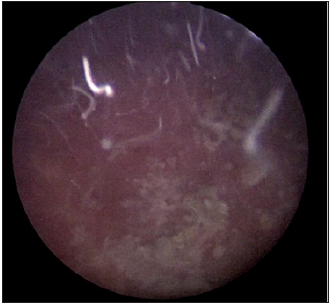

Under general anesthesia, we proceeded to a first progressive dilation of the orifice of the mitrofanoff, which was punctiform, with a hegar dilator until 16FR, then an introduction of a 9.5CH semirigid ureteroscope under visual control, neo-bladder exploration has shown no suspect lesion of the mucosa, the use of a 265μm HOLMIUM Laser fiber down ureteroscope permitted fragmentation of the stone using dusting mode (Figure 4) then fragmentation which were then removed with the zero tip basket. The procedure took 95 minutes and rendered the patient completely stone free (Figure 5). She was discharged the next day.

Figure 5: The end of fragmentation obtaining a stone free bladder.